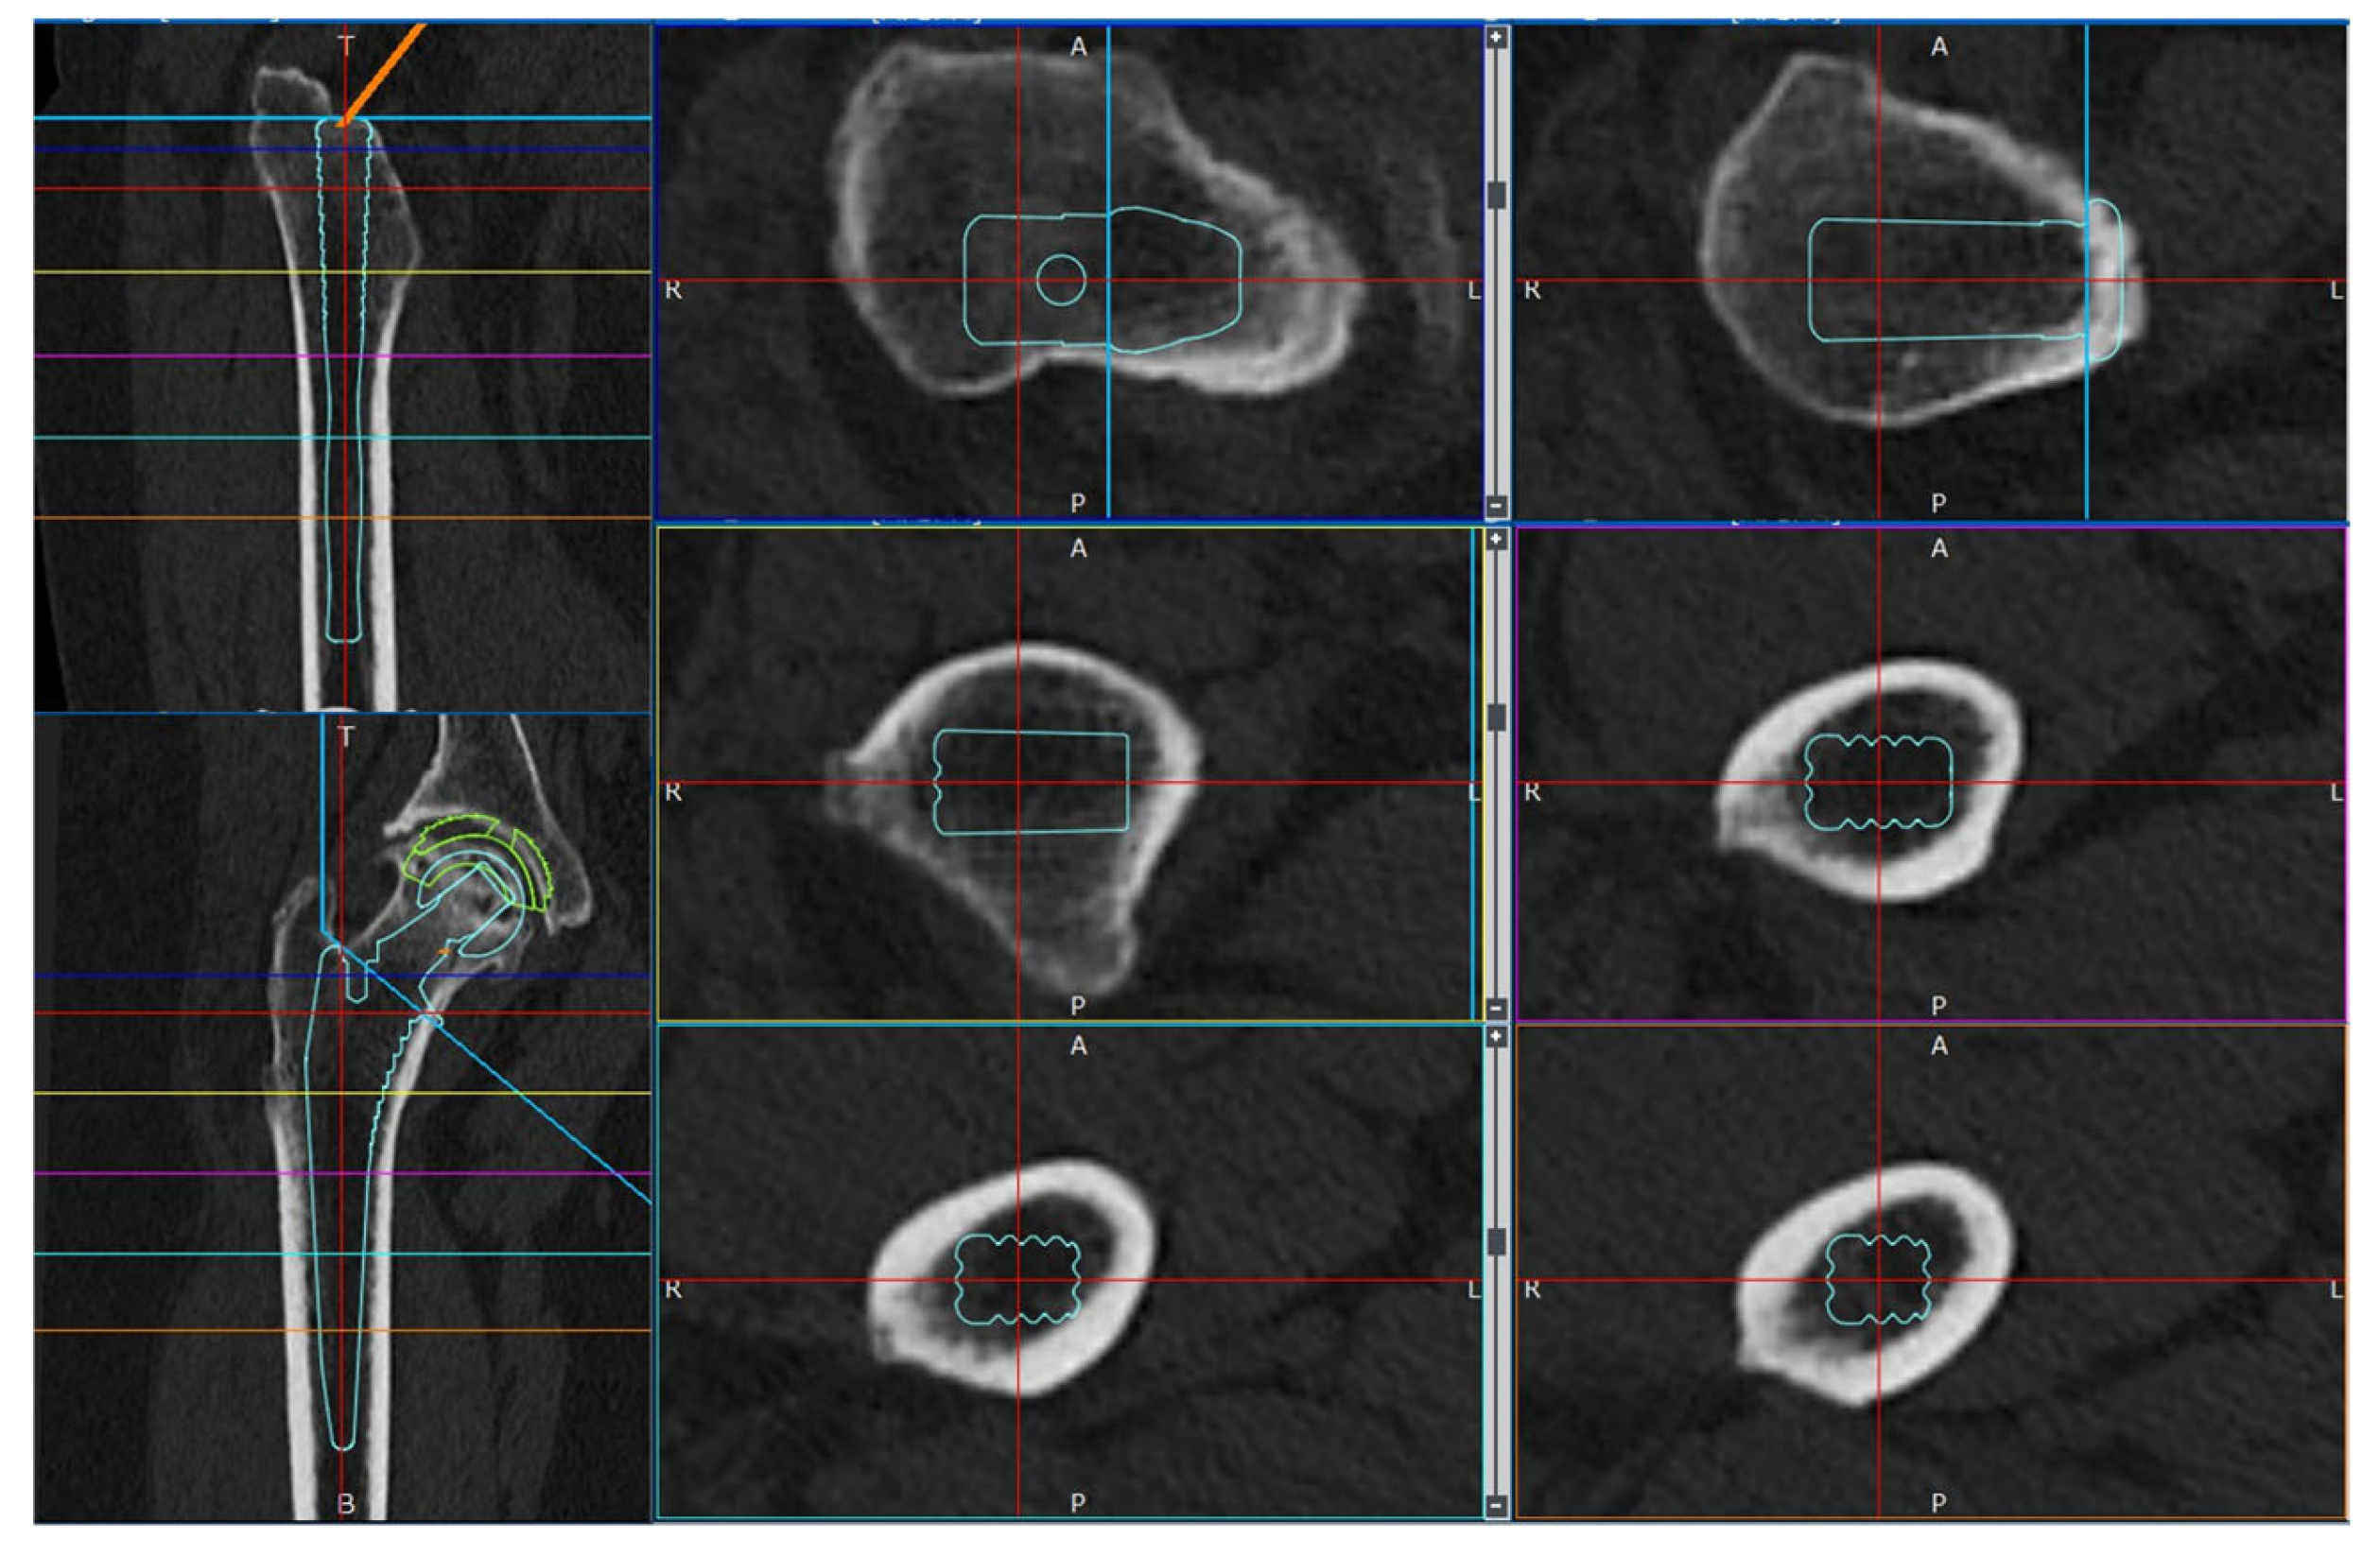

The STL data from the Universia stem were inserted into the removal model to create a cTHA model (Figure 1). The stems were divided based on their length into three groups: (1) short (120 mm stem, hereafter referred to as the S group); (2) normal (130 mm stem, N group); and (3) long (160 mm stem, L group) (Figure 1). In clinical practice, the 130 mm normal stem is the only one used, whereas the short and long stems were newly constructed virtual stems for this simulation. The long stem was selected based on previous studies that recommended a bridging length of approximately 40 mm for fractures or large cortical bone defects [39,40,41], and a stem length of 160 mm was used for verification.

Figure 1.

3D-cTHA model, constructed by inserting a stem into a 3D femoral model after intramedullary nail removal. Three types of stems were used: a short stem (S, 120 mm) with its tip at the same level as the distal screw extraction hole; a normal stem (N, 130 mm) bridging 10 mm beyond the hole; and a long stem (L, 160 mm) bridging 40 mm.

Simulations were conducted under a load to analyze the femoral stress distribution for each stem length. The femoral neck osteotomy and stem placement positions were initially planned using the 3D preoperative planning software, ZedHip (version 17.0.0; Lexi Co., Ltd., Tokyo, Japan) (Figure 2) and were faithfully reproduced in the MF.

Figure 2.

Preparation for cTHA. Preoperative planning was performed using the 3D preoperative planning software, ZedHip (version 17.0.0; Lexi Co., Ltd., Tokyo, Japan).